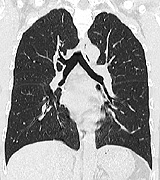

喫煙者向けの測定

Risk Pointer

胸部CTを撮影したデーターよりCOPD(慢性閉塞性肺疾患)の評価ができます。

LAA解析(Low Attenuation Areaの略で、低吸収領域を示す)により

LAA分布(CT画像上の黄色い部分=肺胞にダメージのある部分) がわかりやすく禁煙指導に有用です。